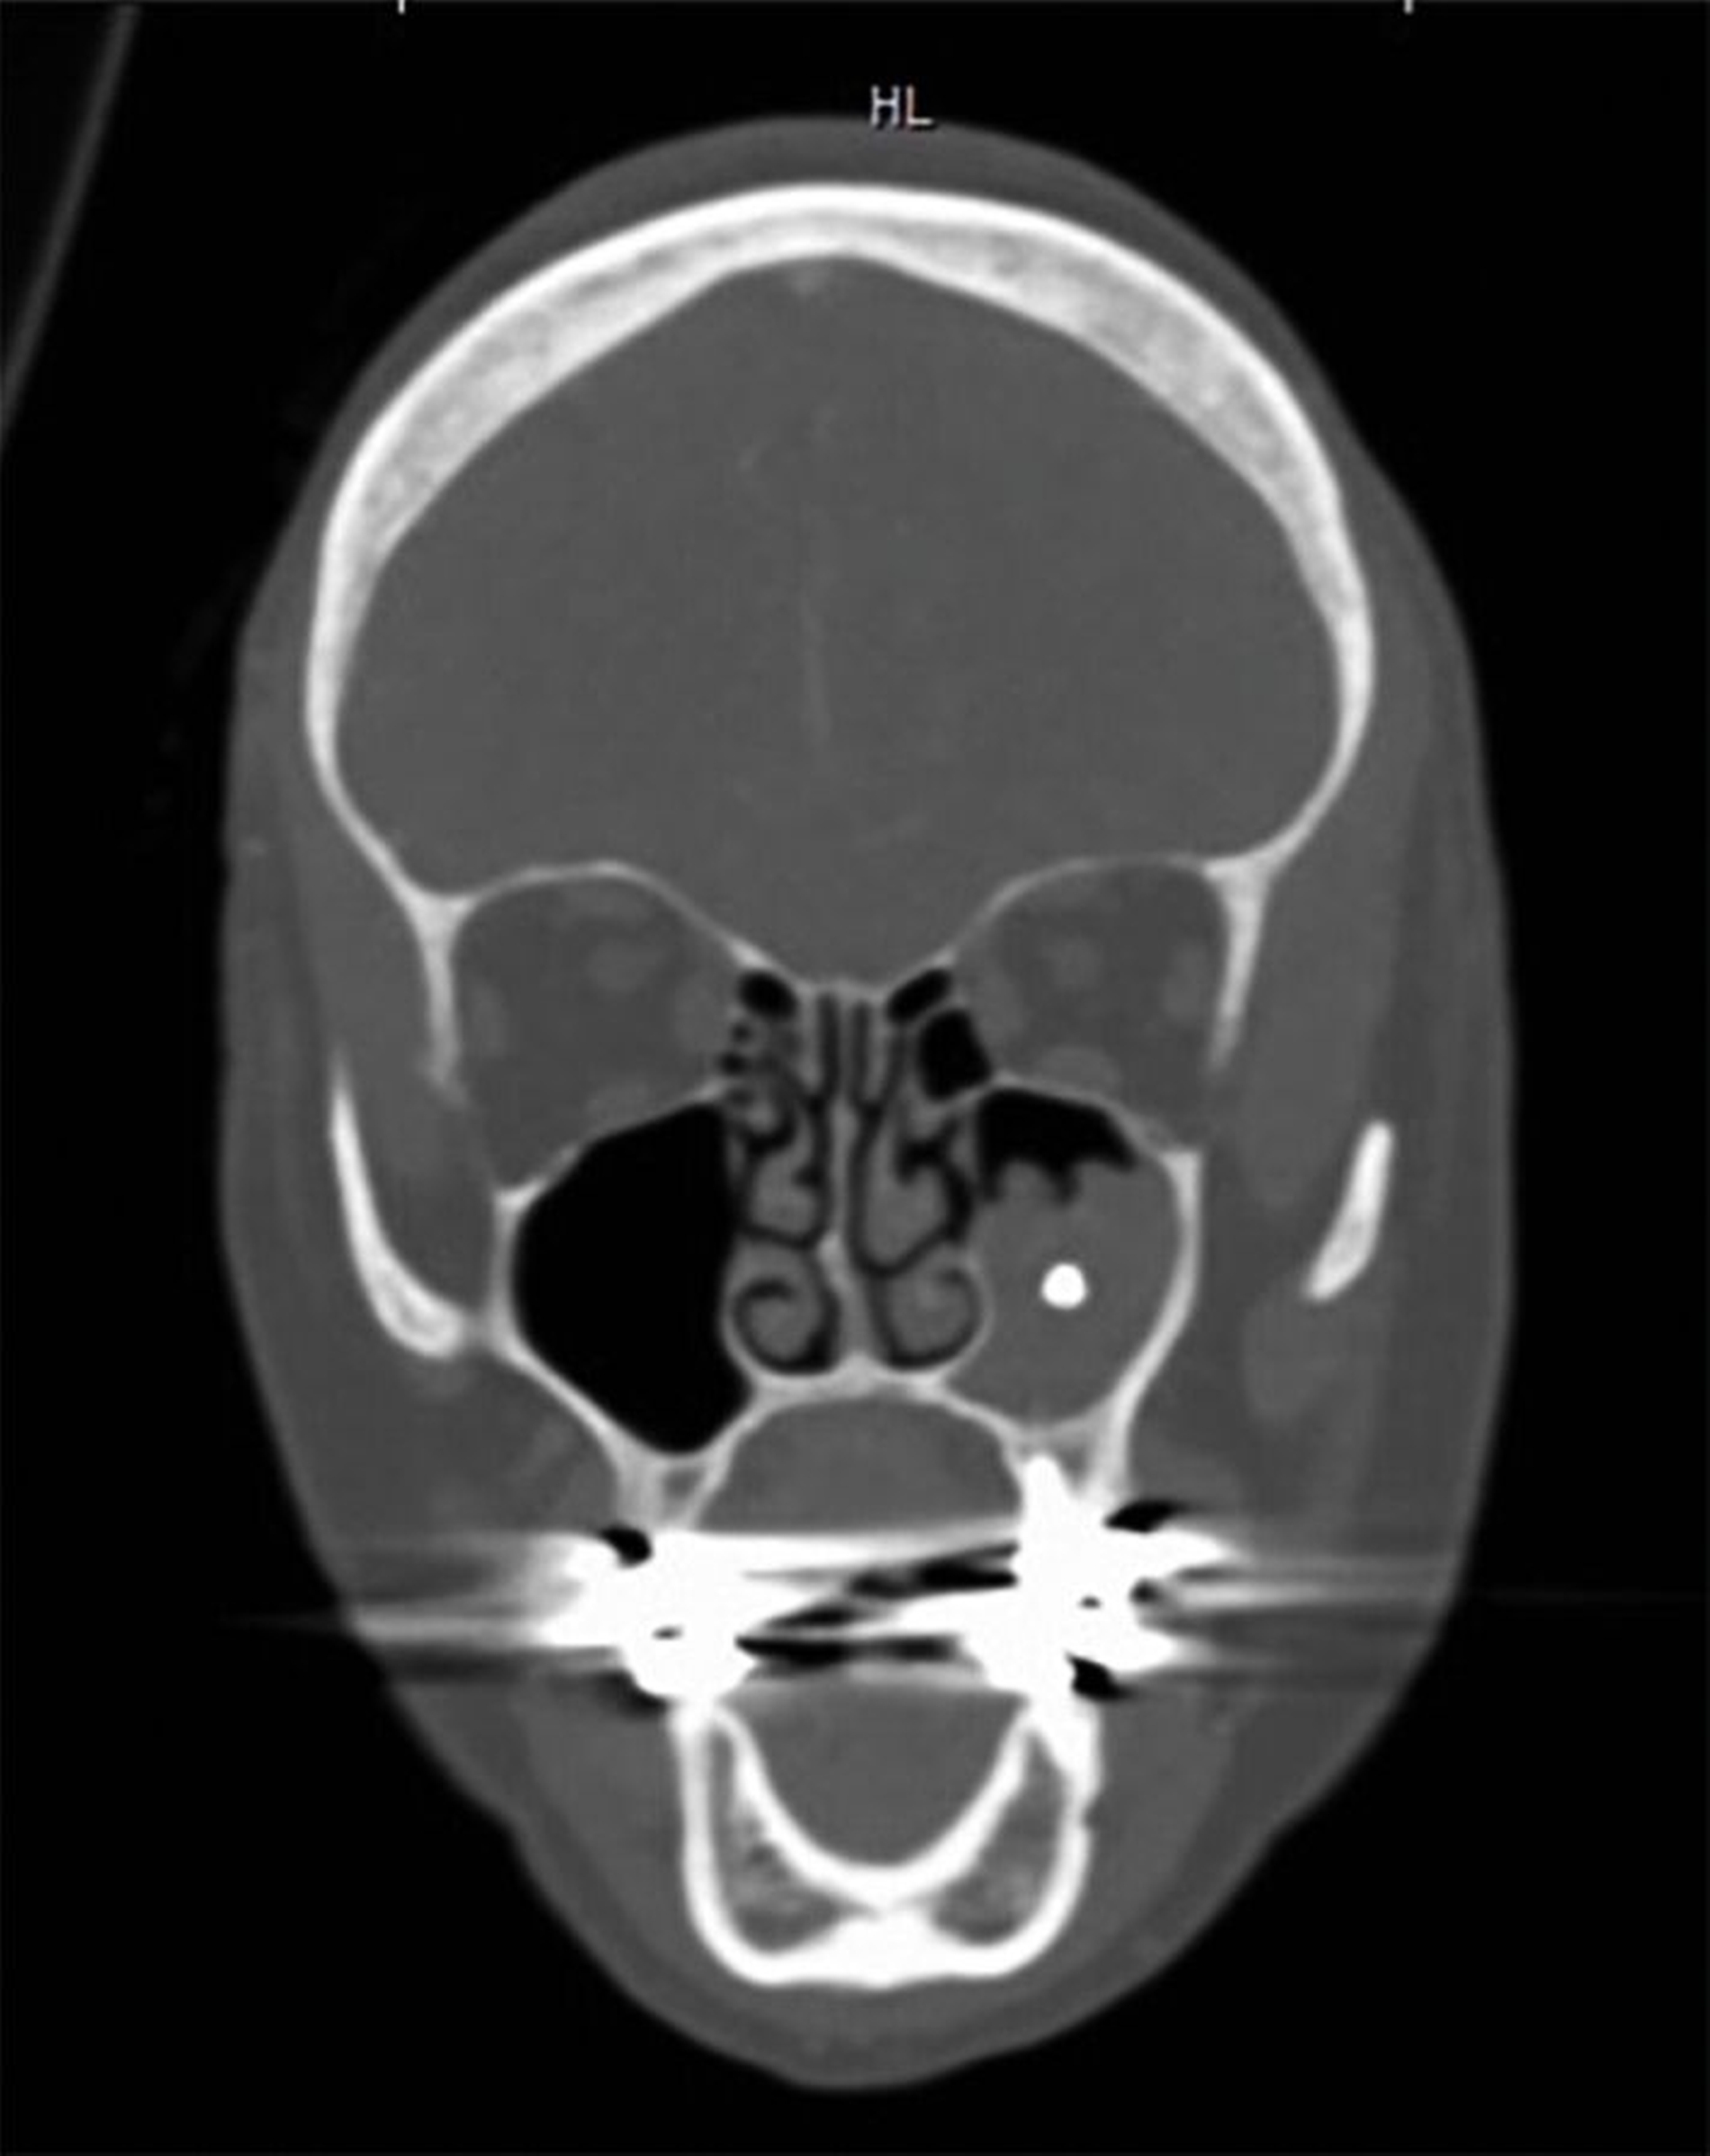

Eine 69-jährige Patientin stellte sich im März 2020 erstmals in der HNO-Abteilung der Uniklinik in Gießen vor. Sie war fünf Tage zuvor aufgrund eines Schlaganfalls in der Stroke Unit stationär behandelt worden, dabei hatte die bildgebende Diagnostik den Zufallsbefund einer Pilzsinusitis in der linken Kieferhöhle ergeben. Die Vorstellung erfolgte zur weiteren Abklärung und möglichen Therapieplanung.

Bei der erneuten Vorstellung in der HNO-Abteilung etwa ein Jahr später berichtete die Patientin über eine seit Monaten bestehende Schwellung prämaxillär links sowie gelegentliche gelbliche Rhinorrhoe. Sie hatte zunächst eine niedergelassene HNO-Kollegin konsultiert, die eine DVT-Untersuchung durchführte, bei der eine Verschattung des linken Sinus maxillaris, verursacht durch eine überstopfte palatinale Wurzelfüllung am Zahn 26, nachgewiesen wurde (Abbildung 2).

Die Guttapercha-Füllung ragte dabei 7,2 mm in den Sinus maxillaris hinein. Die von der HNO-Ärztin veranlasste Begutachtung der DVT-Bilder durch einen niedergelassenen Zahnarzt ergab laut dessen Beurteilung keinen zahnärztlichen Handlungsbedarf. Bei bestehender Beschwerdesymptomatik (wie beschrieben) wurde die endoskopische Kieferhöhlenrevision links in Intubationsnarkose durchgeführt.